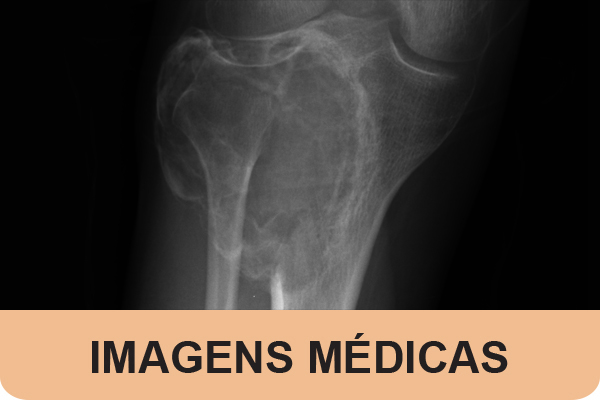

A 21-year-old male presented to the emergency department with right knee pain and swelling. A diagnosis of giant cell tumor of the bone (GCT) was made on magnetic reso...